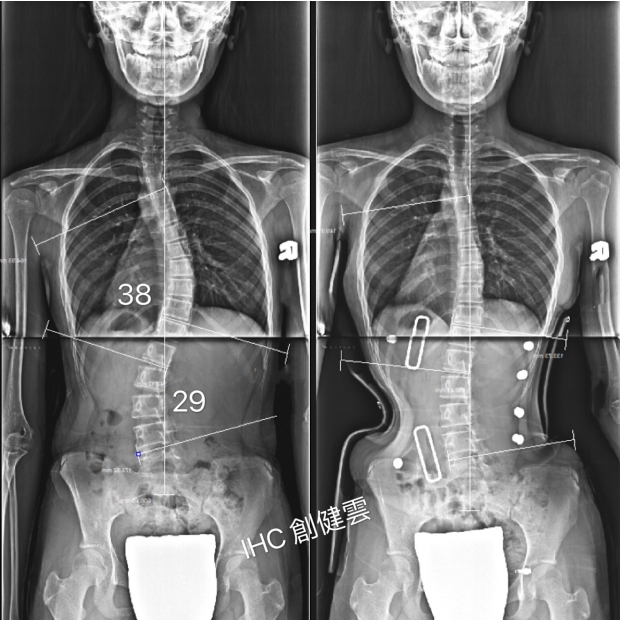

14歲S型脊椎側彎女孩

胸彎38度,腰彎29度

穿背架前 穿上背架後

聲明 : 以上背架矯正案例皆為創健雲團隊親自製作,未經同意請勿任意轉載及使用。任何背架矯治效果因人而異,必須由專家當面諮詢與評估。